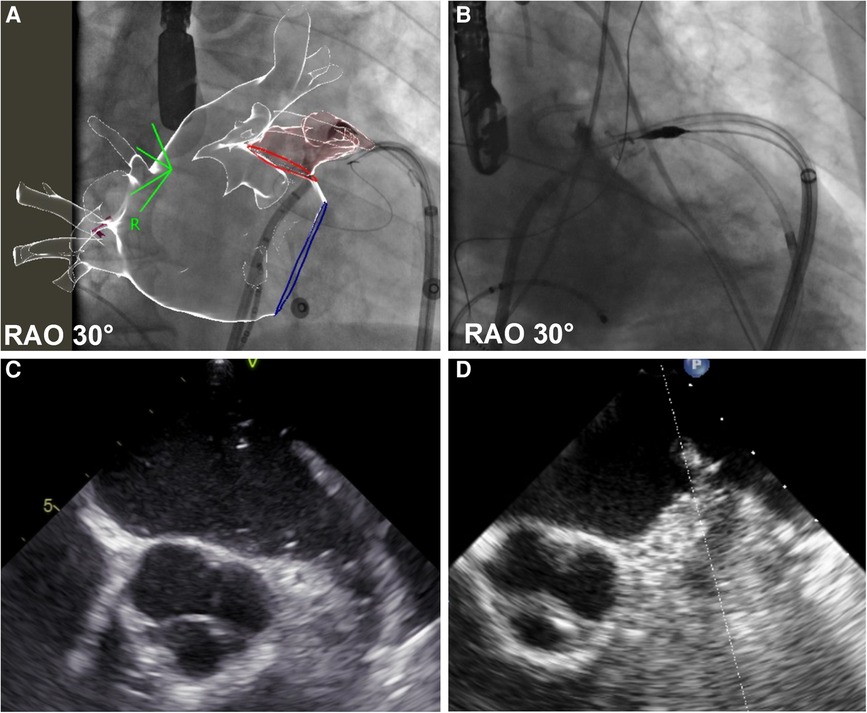

The LARIAT “noose device” was advanced through the epicardial introducer up to the LAA ostium, and angiography was repeated. Then, the loop was closed with echocardiographic and angiographic demonstration of the complete LAA occlusion (see Figure 1).

Figure 1. Before and after left appendage ligation. The figure shows left atrial appendage (LAA) angiography before (panel A—fluoroscopic image, panel C echocardiographic frame) and after (panel B—fluoroscopic image, panel D echocardiographic frame) LAA ligation. In panel A, fluoroscopic images are synchronized with the CT scan reconstruction, previously merged with the electro-anatomical map of the left atrium. Detailed description in text.

All procedures were successfully concluded with complete appendage exclusion after epicardial ligation (see Figure 1), as demonstrated with both transesophageal echocardiography and angiography.